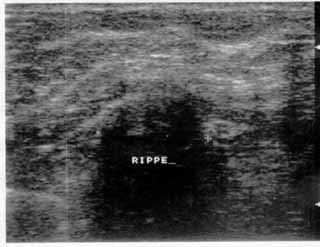

Οι απεικονίσεις των περιστατικών που επιδεικνύονται παρακάτω, έγιναν με κυρτές κεφαλές 3,5 και 5 ΜΗΖ, προκειμένου να φανεί, ότι και με τον εξοπλισμό αυτό, που σιγά-σιγά διαθέτουν όλο και περισσότερα ιατρεία, είμαστε σε θέση να έχουμε ικανοποιητικά αποτελέσματα.

Oι τελευταίες 4 απεικονίσεις έγιναν με ειδικό για μαστό ηχοβολέα linear, εναλλασσομένης συχνότητος 7,5-10ΜΗΖ.